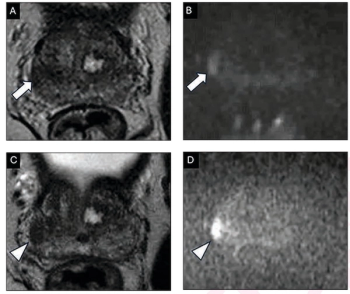

Patients with localized high-risk prostate cancer and midline radiotracer activity in the prostate had over double the incidence of urethral hyperintensity on T2W MRI, according to research presented at the American Society of Clinical Oncology (ASCO) Genitourinary Cancers Symposium (ASCO-GU).